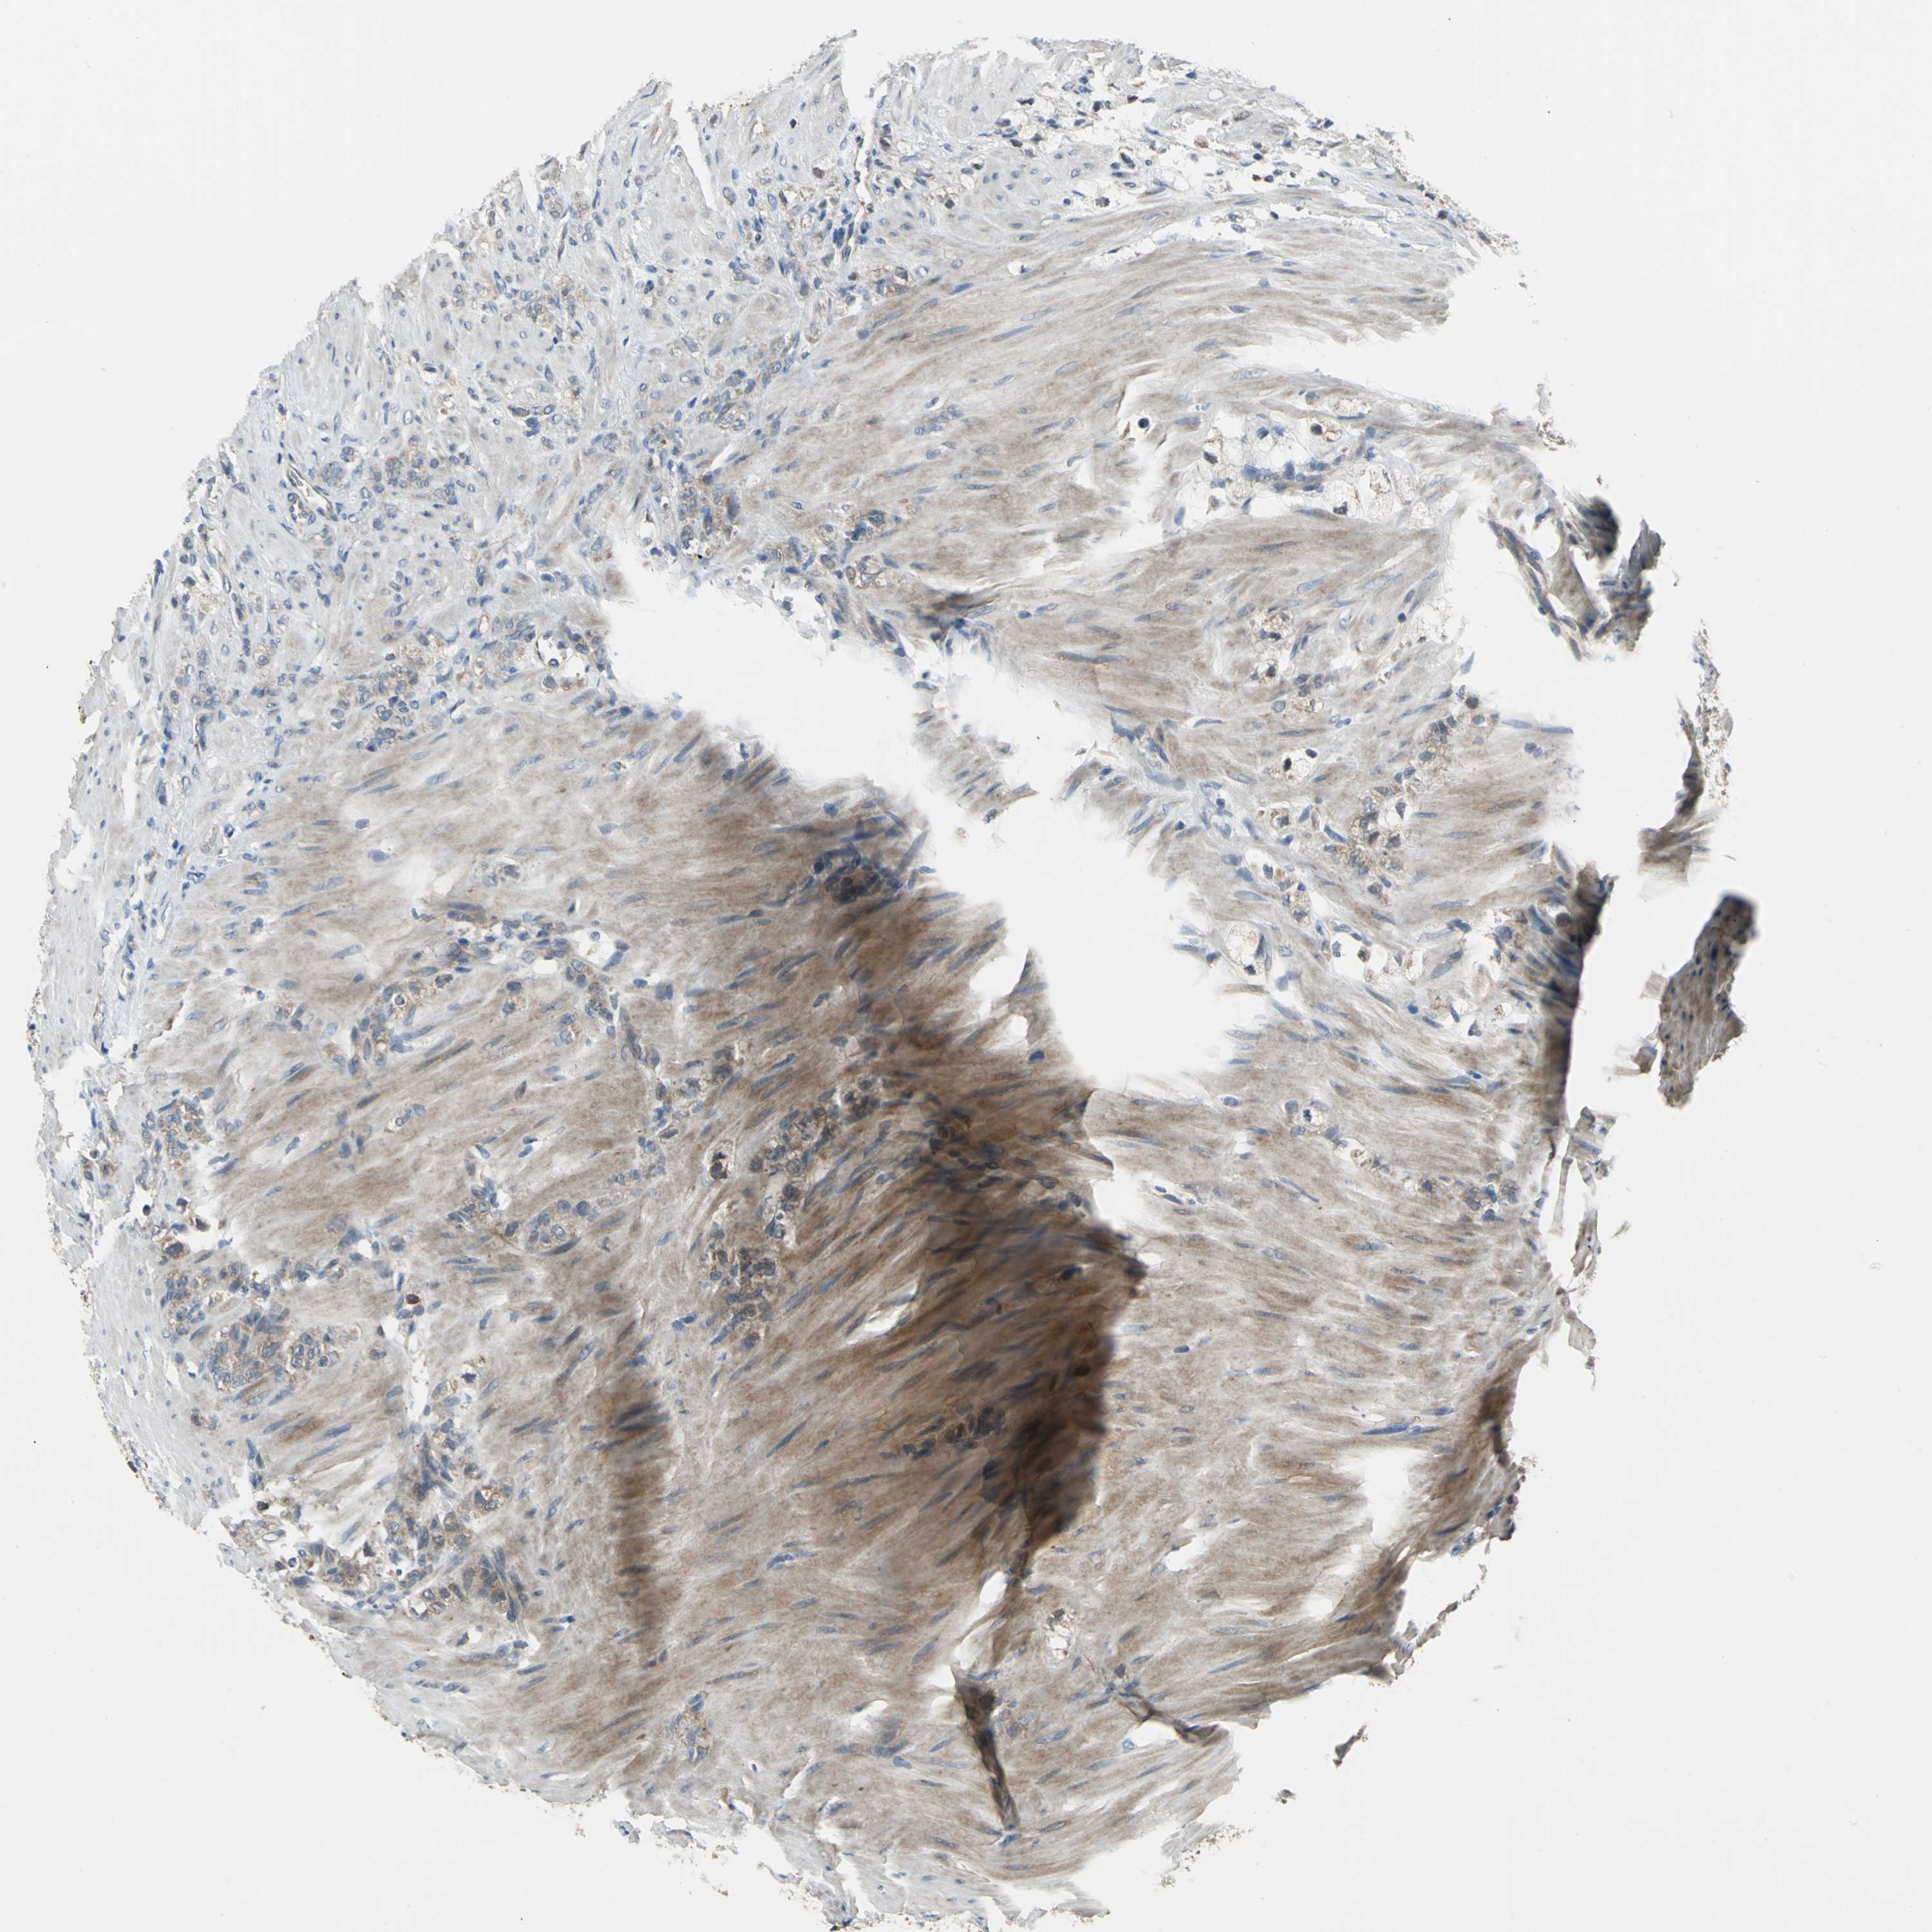

STOMACH CANCER - Protein expressioni

A mouse-over function shows sample information and annotation data. Click on an image to view it in a full screen mode. Samples can be filtered based on level of antibody staining by selecting one or several of the following categories: high, medium, low and not detected. The assay and annotation is described here.

Note that samples used for immunohistochemistry by the Human Protein Atlas do not correspond to samples in the TCGA dataset.

Antibody stainingi

Antibody staining in the annotated cell types in the current human tissue is reported as not detected, low, medium, or high, based on conventional immunohistochemistry profiling in selected tissues. This score is based on the combination of the staining intensity and fraction of stained cells.

Each image is clickable and will lead to virtual microscopy that enables deeper exploration of all samples and also displays staining intensity scores, fraction scores and subcellular localization as well as patient and tissue information for each sample.

Antibody HPA005853

Staining

High

Medium

Low

Not detected

Intensity

Strong

Moderate

Weak

Negative

Quantity

>75%

75%-25%

<25%

None

Location

Nuclear

Cytoplasmic/membranous

Cytoplasmic/membranous,nuclear

Adenocarcinoma, NOS

Adenocarcinoma, High grade